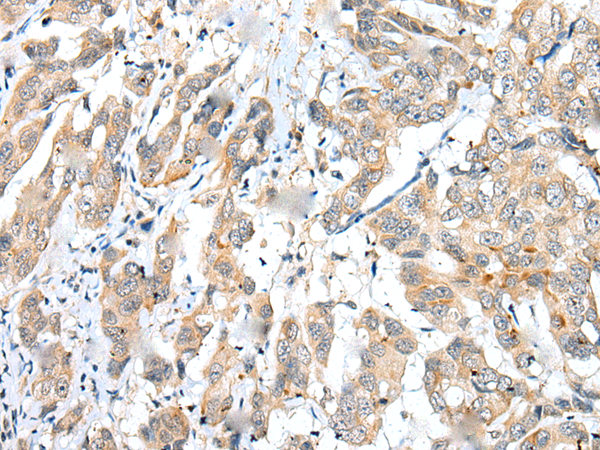

分类: 科研抗体货号: P09096别名:应用: IHC反应种属: Human